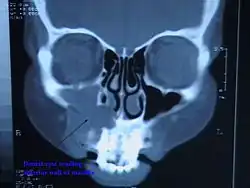

| CT scan through head showing a right periapical cyst | |